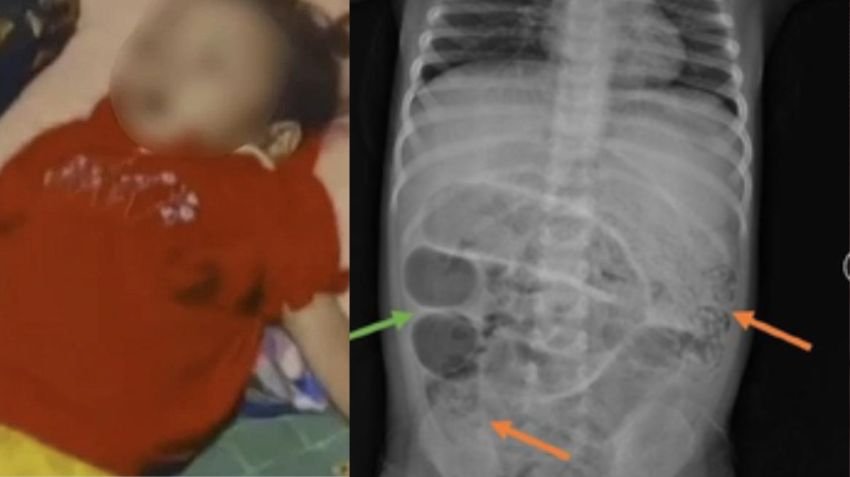

SUKABUMI - Peristiwa meninggalnya Raya, bocah berusia 3 tahun asal Sukabumi akibat infeksi cacing gelang, menyedot perhatian publik dan menjadi sorotan DPR RI.

Anggota Komisi IX DPR RI, Zainul Munasichin, menyebut kejadian tersebut sebagai tamparan keras bagi sistem pelayanan kesehatan di daerah terpencil.

"Saya sangat berduka atas meninggalnya ananda Raya. Ini bukan sekadar tragedi, tapi cermin masih lemahnya akses kesehatan di pedesaan, di daerah-daerah terpencil," kata Zainul saat dikonfirmasi, Kamis (21/8/2025).

Legislator dari Fraksi PKB ini menilai kejadian tersebut menunjukkan bahwa masih banyak wilayah di Indonesia yang belum terjangkau layanan kesehatan secara optimal. Ia meminta agar pemerintah pusat dan daerah segera melakukan pemetaan wilayah rentan dan melaksanakan pemeriksaan kesehatan secara berkala, khususnya di wilayah pelosok seperti Sukabumi.